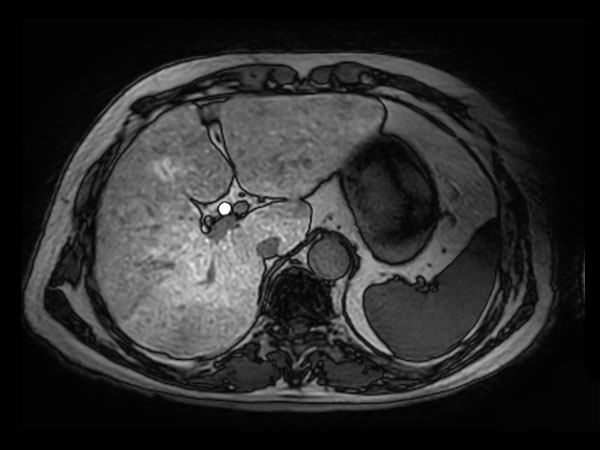

dyn mDIXON XD FFE (pre gado)